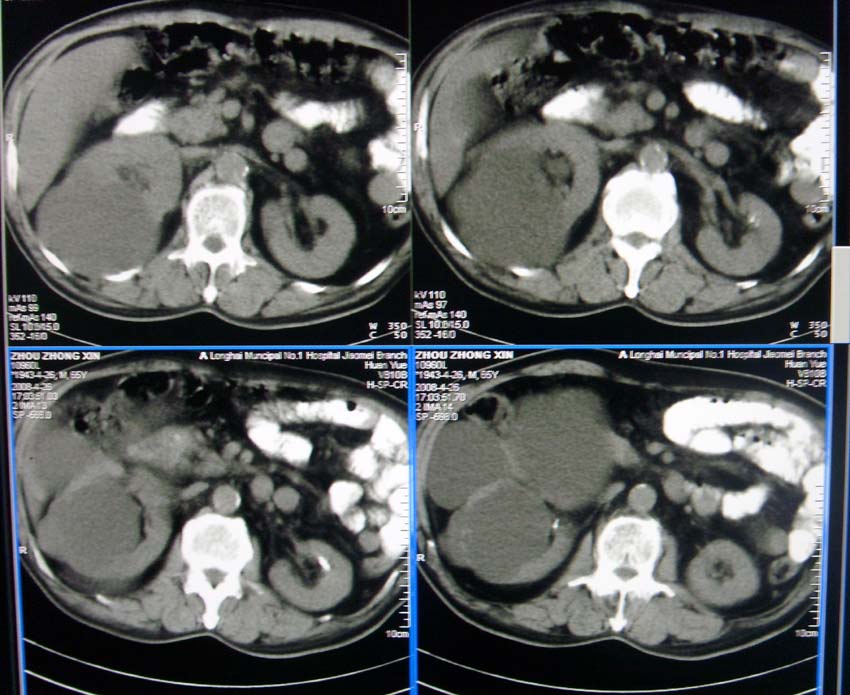

以下是引用liangshusheng在2008-4-27 13:28:00的发言:[br]双肾都有结石,右肾积水波浪状,输尿管积水,建议往下扫

以下是引用zjzjr在2008-4-27 14:25:00的发言:[br]1,右侧多发囊性占位,考虑囊肿可能大。[br]2,肾下部输尿管走行区囊性占位,巨输尿管?建议mru。